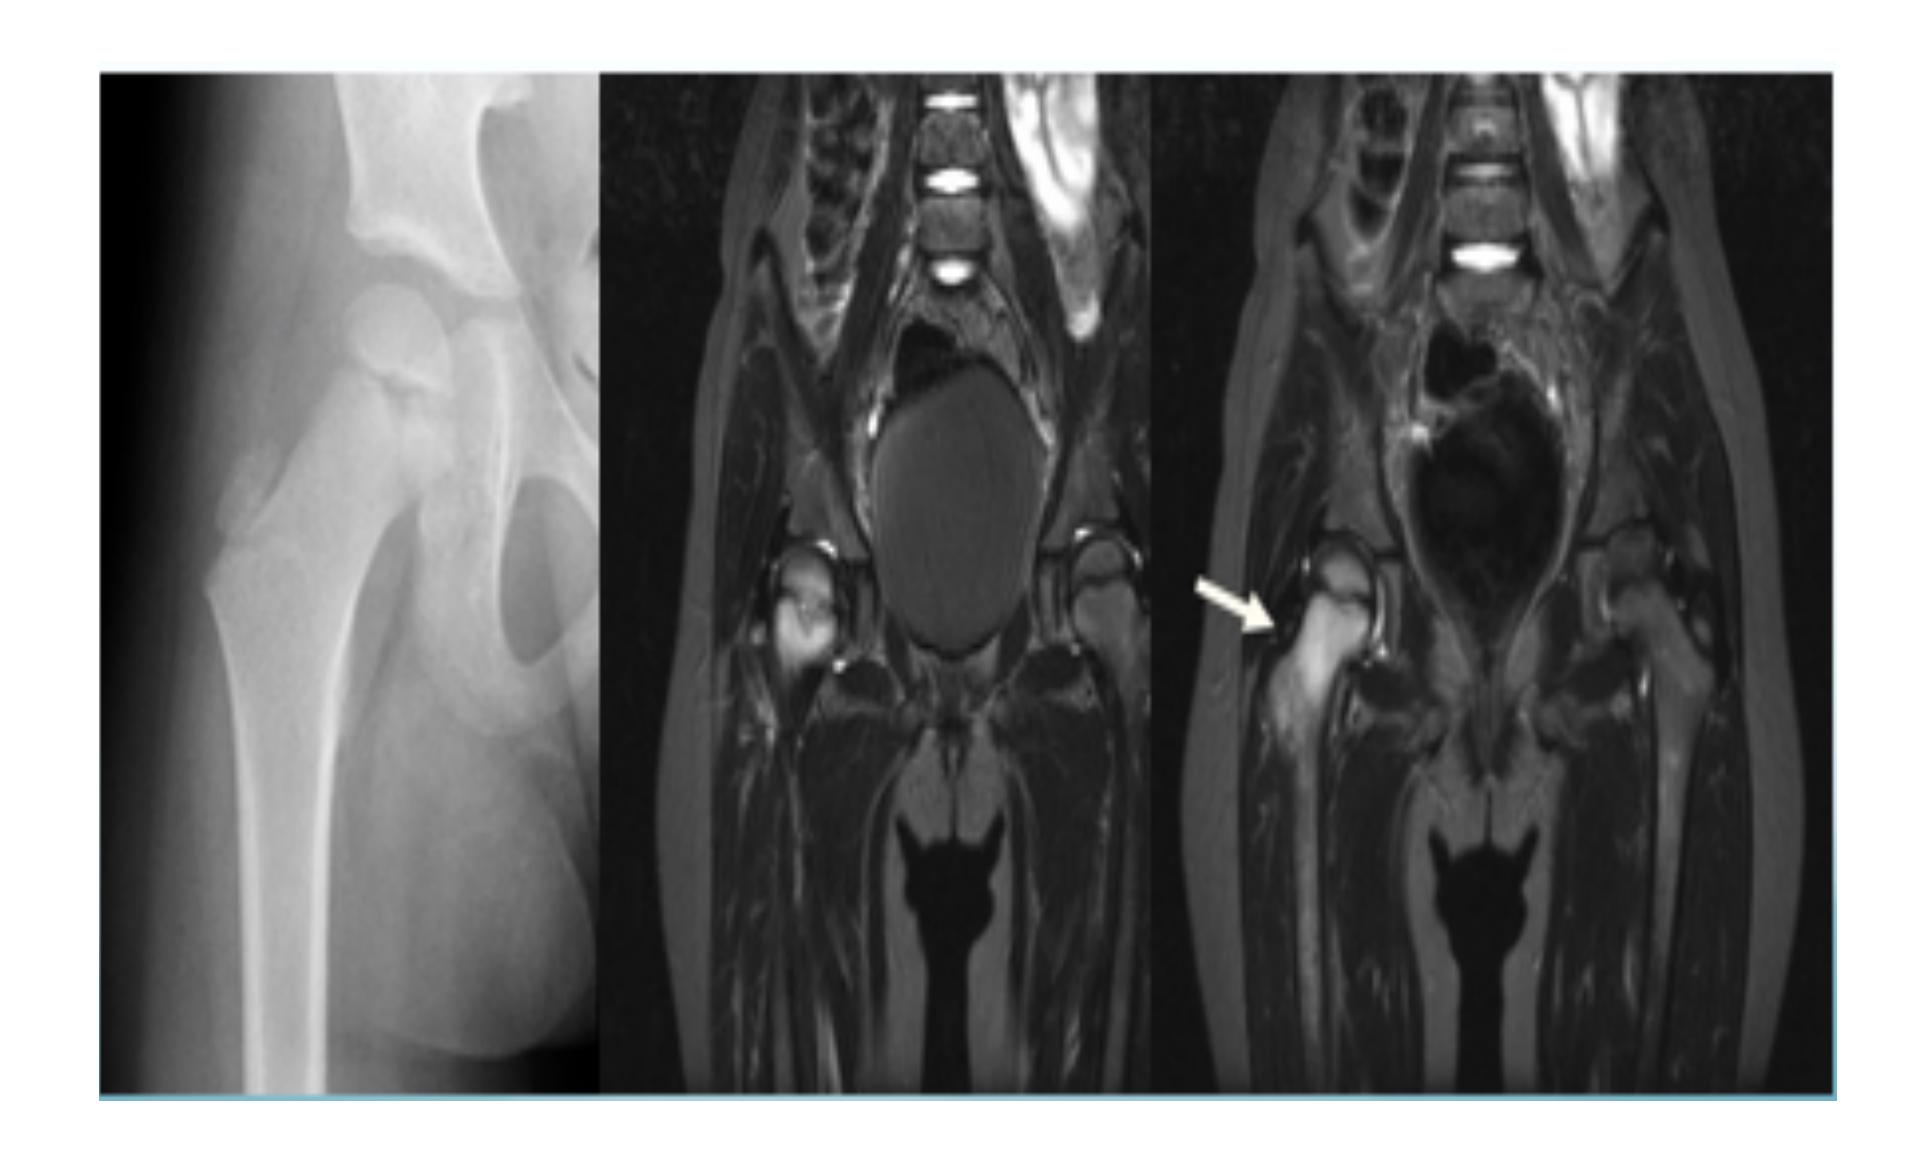

Examination of HIP

https://www.youtube.com/watch?v=Hkqr3mg6IWQ&pp=ygUUSGlwIEV4YW1pbmF0aW9uIE9TQ0U%3D

| Item | Procedure | Additional Information … | Attachments |

| Neonatal Examination for Developmental Dysplasia of the Hip (DDH) - Ortolani Test / Barlow Test (NOT PART OF OSCE) | Ortolani Test Purpose: Reduces a dislocated hip. Expected finding: Feel a “clunk” (not a “click”). Barlow Test Purpose: Dislocates a reduced hip. Expected finding: Feel a “clunk” (not a “click”). | Ortolani Test technique Purpose: Reduces a dislocated hip - Expected finding: Feel a “clunk” (not a “click”) ![]() Barlow Test technique Purpose: Dislocates a reduced hip - Expected finding: Feel a “clunk” (not a “click”) ![]() Combined Ortolani/Barlow technique ![]() ![]() | |